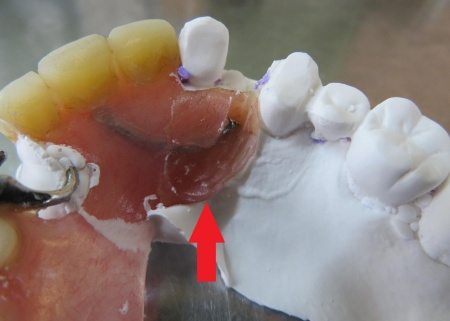

①増歯:入れ歯にプラスチック製の人工歯を加え、折れた歯を補う処置

②新たなクラスプの製作:入れ歯の安定を図るため、左上の前歯から4番目の歯にかけるバネを追加する

最後に入れ歯を装着し、痛みや違和感がないか、見た目や噛み合わせに問題がないかを確認し、治療を終了しています。

治療中画像 治療中画像 治療中画像 治療中画像